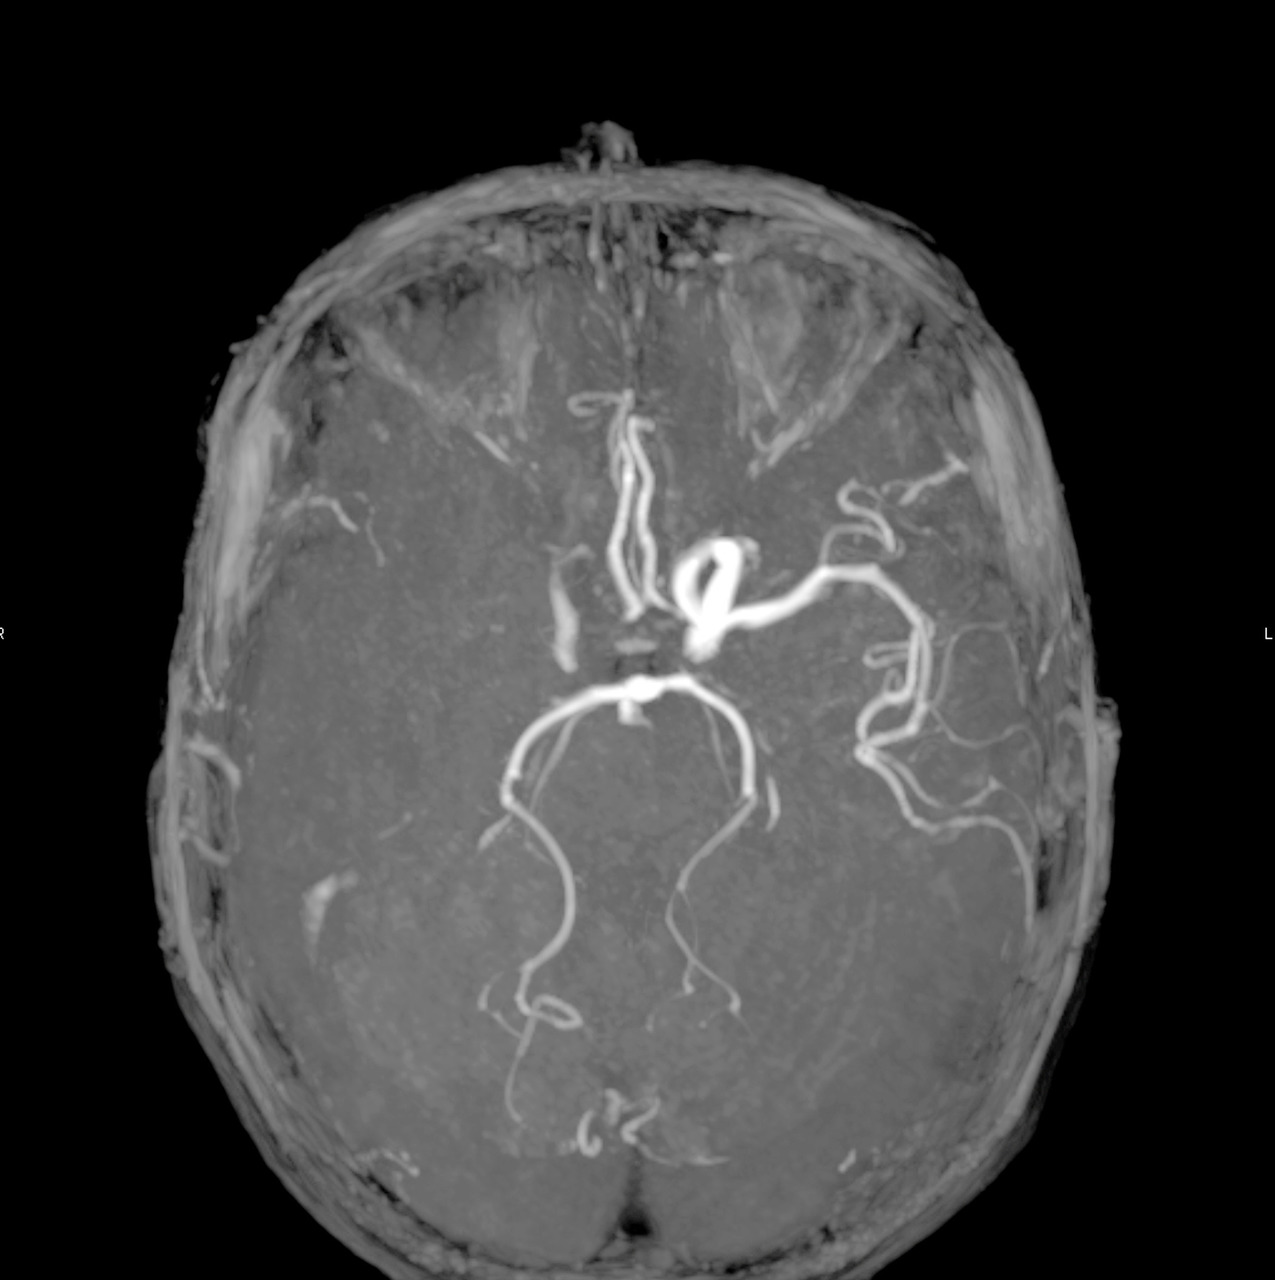

En 2015, cinq essais thérapeutiques ont prouvé l’efficacité de la thrombectomie mécanique en association à la thrombolyse IV dans le traitement des AVC ischémiques avec occlusion des artères de gros calibre de la circulation antérieure (artères carotide interne et moyenne proximale, fig. 1 à 4).6 La thrombectomie mécanique peut être réalisée avec des stents retriever (stents déployés mais non implantés) et/ou des dispositifs d’aspiration. L’effet de la thrombectomie mécanique est majeur, avec un nombre de patients à traiter de 2,6 pour éviter la dépendance,6 alors qu’il est estimé que pour 1 000 patients traités par thrombolyse IV, 41 éviteront la mort ou la dépendance.7 La thrombolyse IV est par ailleurs limitée par une augmentation du taux d’hémorragie intracrânienne symptomatique responsable d’une surmortalité durant les 7 premiers jours ; de faibles taux de recanalisation (au mieux 30 %, alors que la thrombectomie mécanique permet des taux de 80 à 90 %) en cas d’occlusion proximale intracrânienne ; sans oublier de nombreuses contre-indications (traitements anticoagulants, chirurgie récente…).